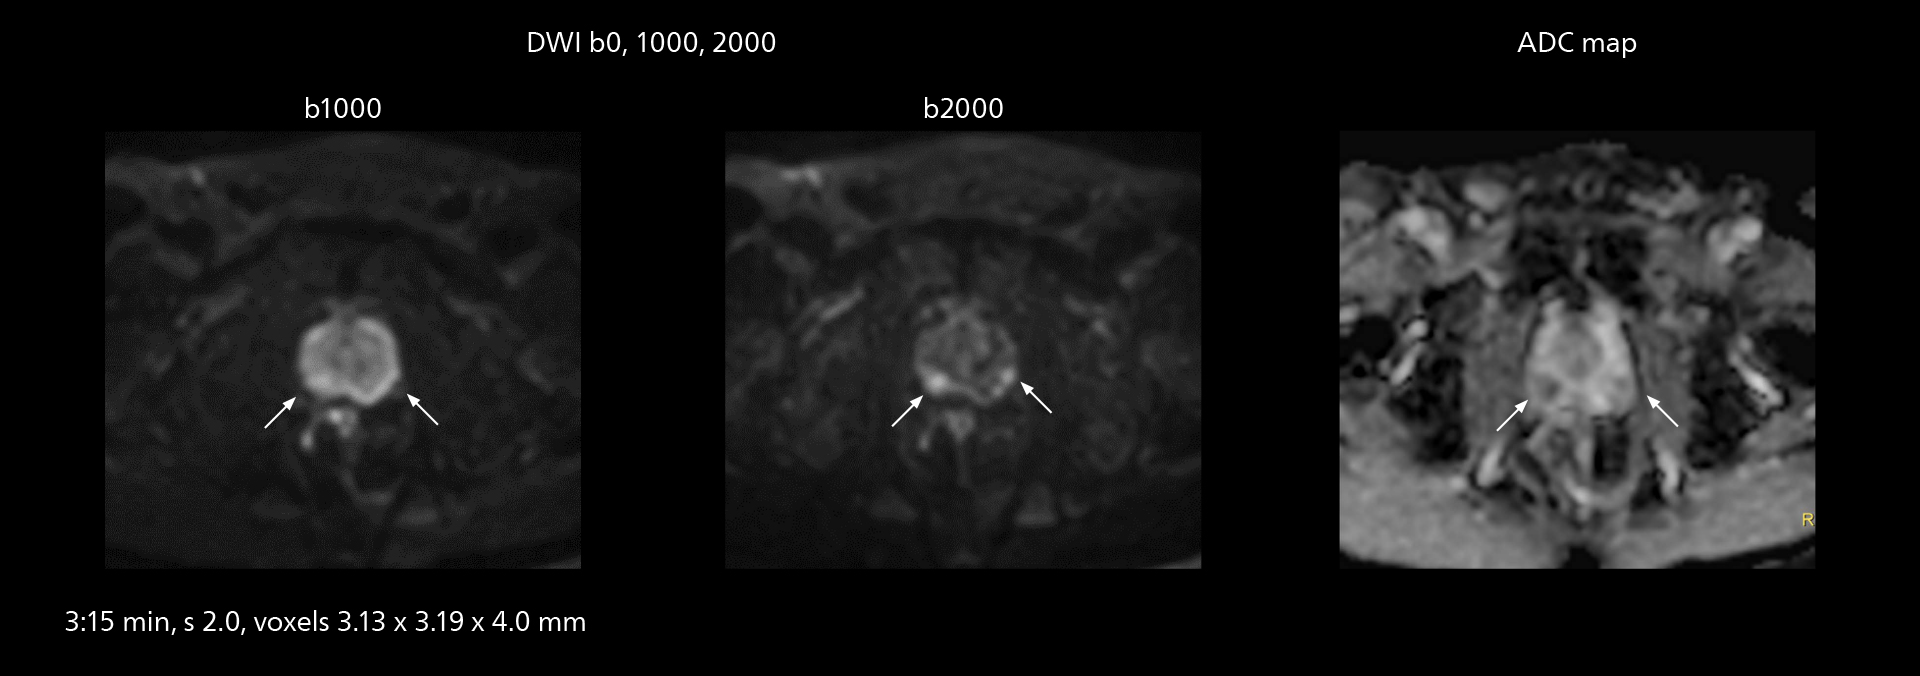

The high performance of the Vega HP gradients is particularly impressive in DWI. “The Vega HP gradients enable us to scan faster and use b-values as high as 2000, for example in prostate DWI and in DWIBS, which provides image quality that is remarkably improved over the previous system and we are able to more easily see lesions.”

MRI of prostate

Examples of prostate imaging showing faster scan times and improved resolution illustrate the power of SmartPath to Elition X in this case of prostate cancer with PI-RADS score 4.